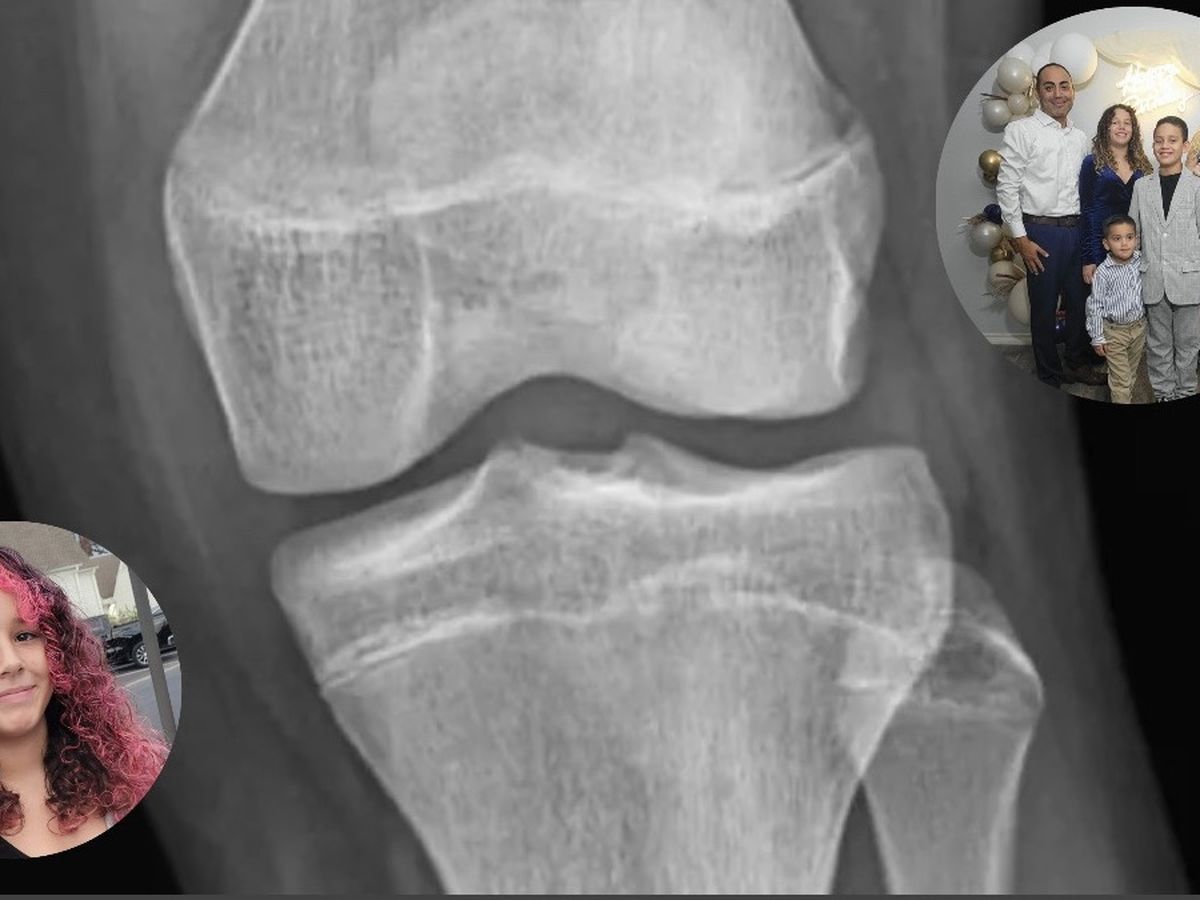

My 13-year-old niece, Caroline, has always been full of energy, especially when it comes to playing basketball and soccer. Unfortunately, while playing the sports she loves, she suffered a significant knee injury that requires surgery. She has torn both meniscus ligaments and will need to undergo ACL reconstruction. To make matters more complicated, Caroline has a rare and serious tear called a “bucket handle tear flip,” which makes her recovery even more complex.